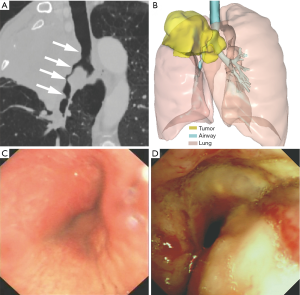

This retrospective study was approved by our institutional review board, and written informed consent was waived. We analyzed the clinical data of patients with malignant airway stenosis involving the carina or bronchi who were treated with implantation of metallic segmented airway stent customized with the aid of 3D printing from January 2017 to May 2019. Patients with tracheoesophageal fistula or patients who underwent both airway and esophageal stenting were excluded. Finally, 12 patients were included in this study. Surgery could not be performed in these patients due to advanced tumor stages. The therapeutic strategy of airway stenting was confirmed by a multidisciplinary discussion attended by thoracic surgeons, pulmonologists, interventional radiologists, and anesthetists. The customized stent was used when the airway stenosis was anatomically complex and difficult to treat with a commercial stent. The use of the stent was approved by the institutional review board and all patients provided written informed consent prior to the procedure. Preoperative chest CT and flexible bronchoscopy were performed to help confirm the location, severity, and range of the stenosis, as well as the anatomical relationship between the airway and the surrounding structures (Figure 1A,B,C,D). The diagnosis of malignant tumors was based on the pathological biopsy results. The 7th American Joint Committee on Cancer/Union for International Cancer Control (AJCC/UICC) staging systems were used to evaluate the tumor stage of these patients.

All patients underwent 64-slice multidetector spiral CT (uCT760; United Imaging Healthcare, Shanghai, China) of the thorax in a supine position during end-inspiration. The scanning parameters were as follows: tube voltage, 120 kVp; tube current, 250 mA; rotation time, 0.35 s; pitch, 0.6; slice thickness, 1 mm; imaging field-of-view, 320 mm. Imaging data gathered from the chest CT scan was used to reconstruct 3D images of the airway using the surface rendering technique with the use of computer-assisted design software (Vitaworks, Shanghai, China). The airway and tumor were then assigned different pseudo-colors, and the image was converted into a 3D stereolithographic (STL) file (Figure 1B). Afterwards, the 3D reconstruction data was entered into a 3D printer (RS600, Union Tech, Shanghai, China) to create an airway mold that was matched 1:1 based on the anatomical characteristics of each patient’s airway with photosensitive resins (Figure 2A).